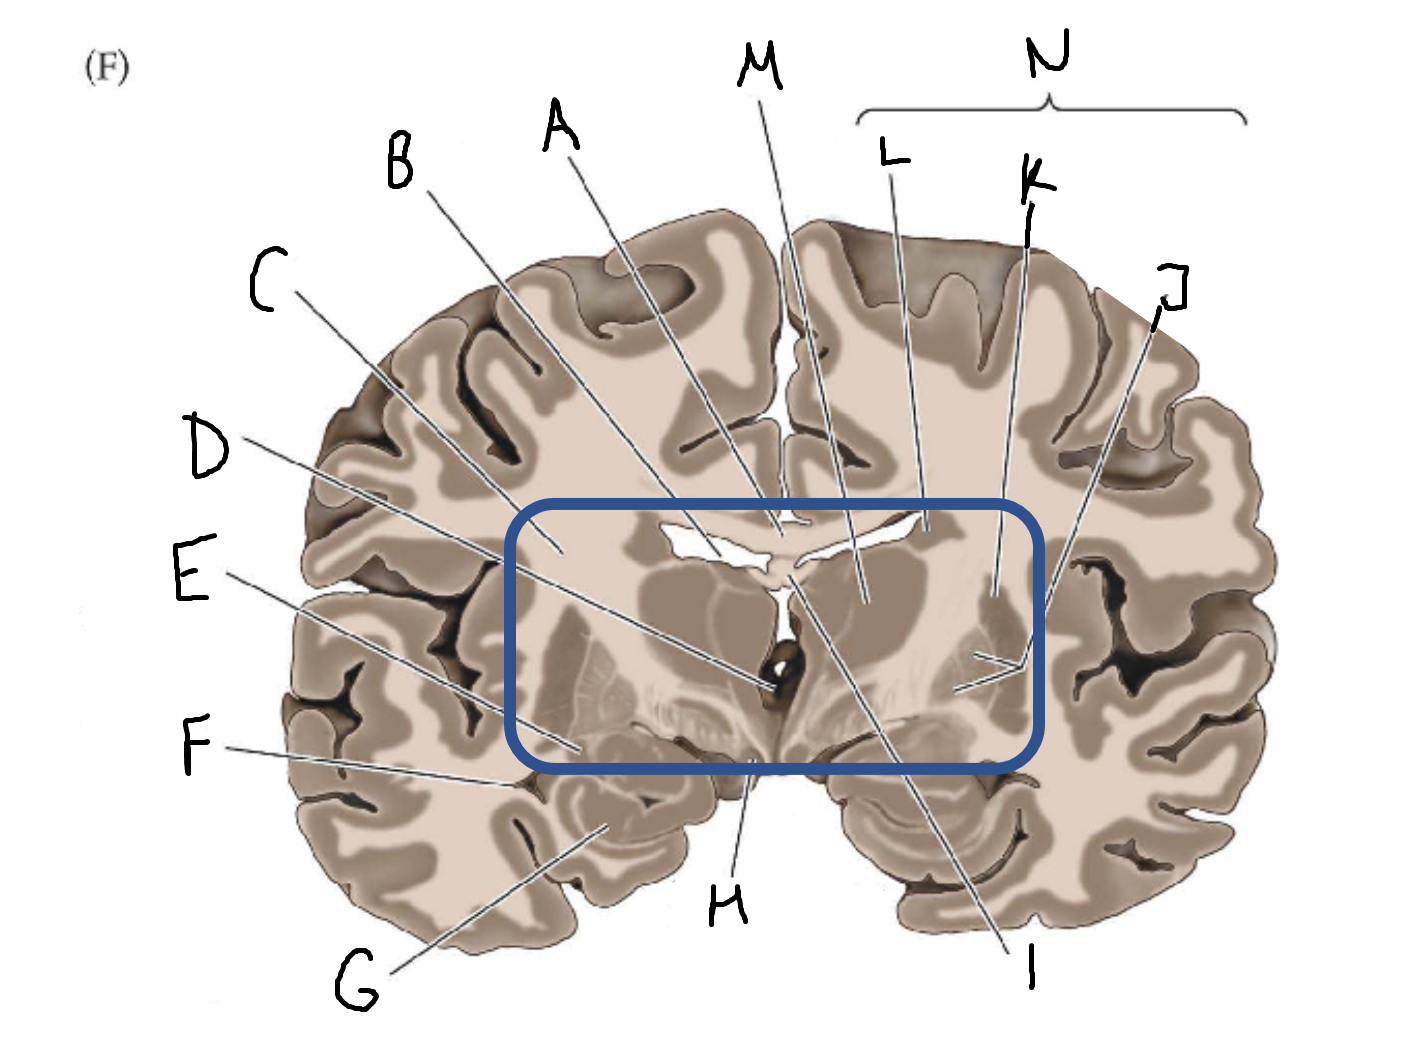

A

corpus callosum

B

lateral ventricle

C

internal capsule

D

third ventricle

E

tail of caudate nucleus

F

lateral ventricle

G

hippocampus

H

mammillary body

I

fornix

J

globus pallidus

K

putamen

L

caudate

M

thalamus

N

basal ganglia